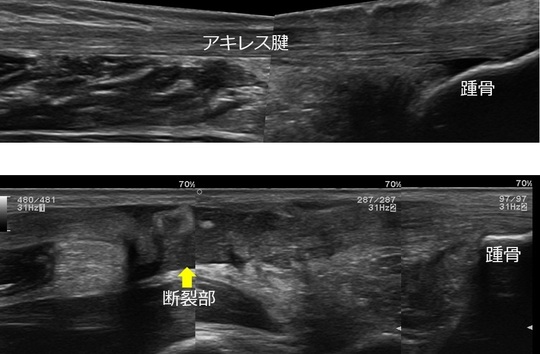

アキレス腱断裂のエコー画像(上:健側 下:患側)

痛みの原因を問診・視診・触診および徒手検査法に合わせて超音波観察装置(エコー)を用いて正確に判断します。そして痛みの原因を判断したうえで、その痛みに対し適切な施術を行っていきます。